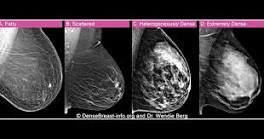

Her breast density camouflaged her cancer. She says new FDA regulations are "a gift." "If I have dense breast tissue, am I more prone to get cancer?" CBS News New York's Kristine Johnson asked. "The answer is, yes, you probably are ...

Columbia University School of Nursing dean says breast density camouflaged her cancer ... York's Kristine Johnson spoke to a breast cancer survivor who says she thought she was cancer-free for years, but that wasn't always the case.